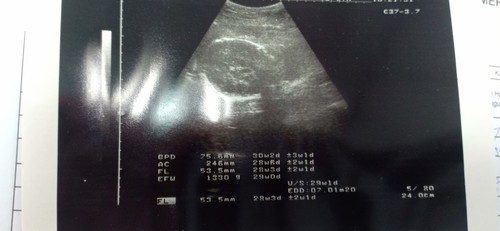

Hi mummys..just nak tanya sekarang saya da 28 weeks++..tadi doctor ada scan..nak tahu berat baby yang tulis EFW tu ke?normal ke tak berat baby saya sebab berat asyik turun tiap2 kali check up merah jer nurse tulis?

Ok dah tu 1.33kg, sy dlu 28w ngam² 1kg.baby lahir 2.5kg